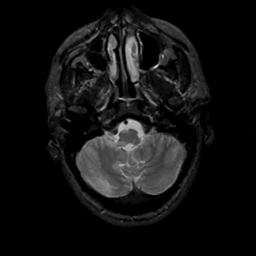

MR Study #10, April 28, 1991 -- Slice #8

[Home][Help][Clinical][Tour 1][Tour 2] Slice 8